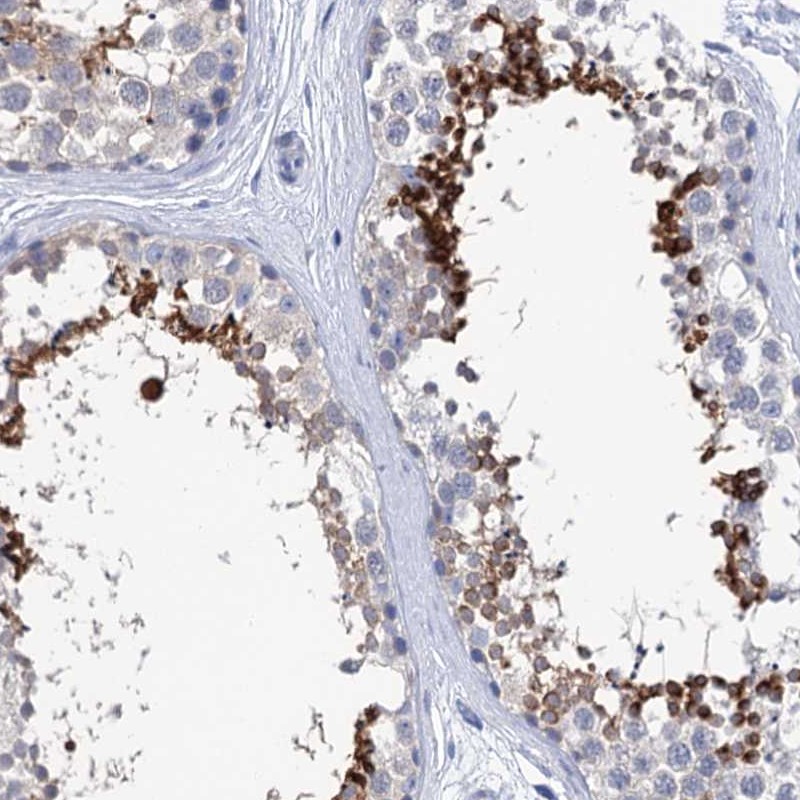

Immunohistochemistry analysis in human testis and prostate tissues using Anti-SPATA7 antibody. Corresponding SPATA7 RNA-seq data are presented for the same tissues.